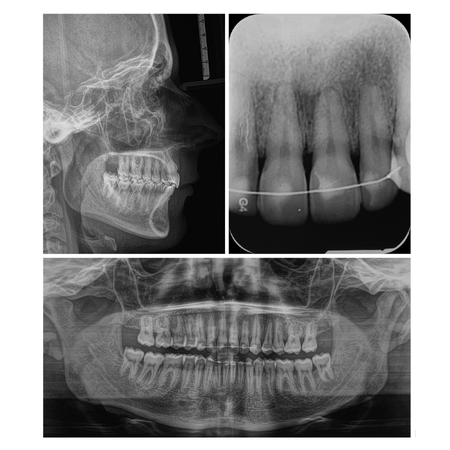

Fechamento de espaços com mini-implantes em paciente Classe III esquelética com agenesia dentária múltipla: relato de caso

INTRODUÇÃO: O gerenciamento dos espaços das agenesias dentárias é frequentemente relatado como um desafio adicional para o tratamento ortodôntico e, quando associado à má oclusão esquelética, torna o tratamento mais complexo. OBJETIVO: Neste relato de caso, objetivou-se apresentar um tratamento ortopédico seguido de tratamento ortodôntico compensatório de um paciente Classe III esquelética severa com agenesia dentária múltipla. RELATO DE CASO: Paciente do sexo masculino, com...

Space closure with mini-implants in a skeletal Class lll patient with multiple tooth agenesis: case report

INTRODUCTION: Space management of tooth agenesis is often reported as an additional challenge for orthodontic treatment and, when associated with skeletal malocclusion, makes the treatment more complex. OBJECTIVE: The objective of this case report was to present an orthopedic treatment followed by comprehensive orthodontic treatment of a severe skeletal Class III patient with multiple tooth agenesis. CASE REPORT: A 14-year-old male had an atypical treatment plan, starting with facemask...